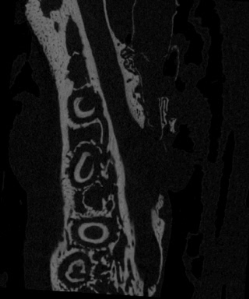

The projection images are then processed using computer software (typically based on a modified Feldkamp Cone Beam reconstruction algorithm) to show the internal structure of the object nondestructively. This series of images is typically called the reconstructed images or cross sections (figure 2).

Reconstruct the Projection Images into Virtual Slices

The process of computing the internal structural information from the projection images is known as reconstruction. This procedure results in a stack of reconstruction images (also referred to as “cross-sectional images” or “slices”). The most prolific reconstruction algorithm is the Feldkamp, Davis, and Kemp (FDK) cone beam reconstruction algorithm which is a form of filtered backprojection (FDP). These cross-sections can then be used to view the internal features, analyzed, reconstructed into virtual 3D models, made into movies, printed into 3D models and more.

Cross sectional images of snow leopard skull (see Image of the Month April 2015)